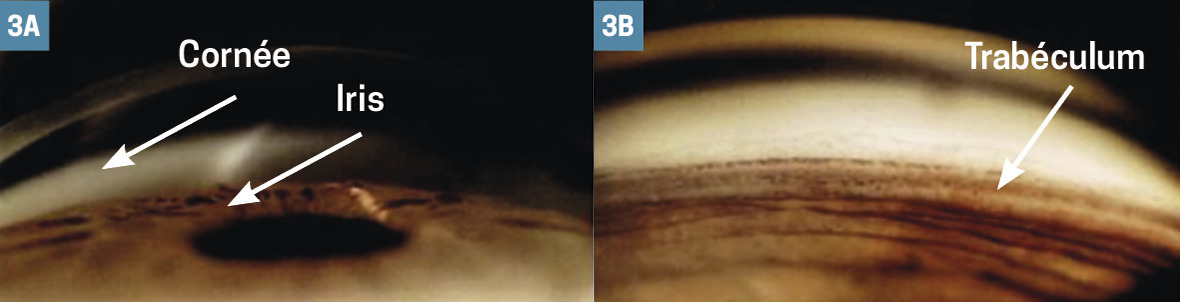

– gonioscopie (fig. 2 et 3), examen indolore qu’on réalise en posant une lentille sur l’œil après anesthésie par instillation de collyre. Il montre l’angle entre l’iris et la cornée et détermine le type de glaucome ;